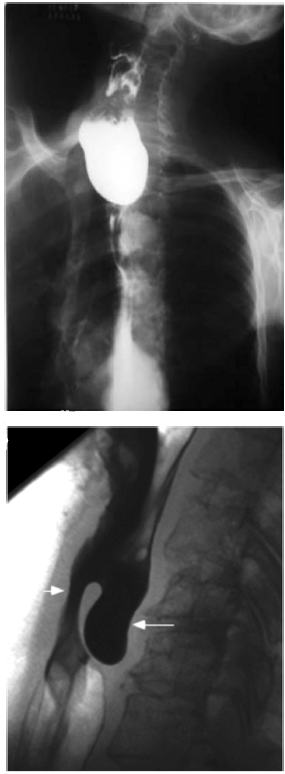

Disponível em: <www.scielo.br>. Acesso em: 16 fev. 2023.

Um paciente de 71 anos de idade apresentou queixa de disfagia cervical, associada a deglutição ruidosa, regurgitação, abaulamento cervical esquerdo, acessos de tosse, halitose e emagrecimento progressivo há três anos. Ele, então, procurou o cirurgião de cabeça e pescoço para investigar essa sintomatologia, o qual optou pela realização de exames de imagem, que evidenciaram as imagens apresentadas.

Qual é a hipótese diagnóstica mais plausível?